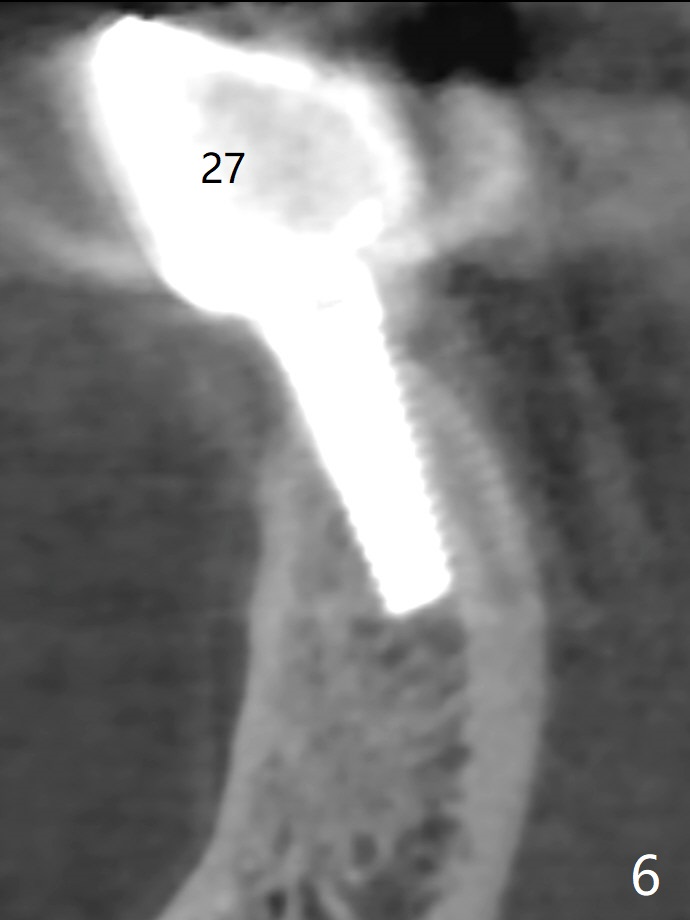

A 67-year-old man with history of chronic periodontitis and bruxism returns to clinic requesting implant for the tooth #20 with mobility (Fig.1). To assure No Deviation of implant placement, Lindamann bur will be used to remove the most coronal of the buccal aspect (Fig.2 *, 3 pink dashed line) of the thick lingual plate (L) during osteotomy. To reduce bone loss (Fig.4 *) associated with residual cement (Fig.4,5 arrowheads) of the tissue-level implants, a bone-level one (SM) will be used at #20. Check whether the nearby implant (#19) has infection clinically and bone graft if needed. Buccolingual threads of the #27 implant are also exposed 3 years 9 months post cementation (Fig.6). An ideal treatment is probably to remove the 4.5x17 mm tissue-level implant and place a 3.8x10 mm bone-level one deeper and a little mesial with bone graft.